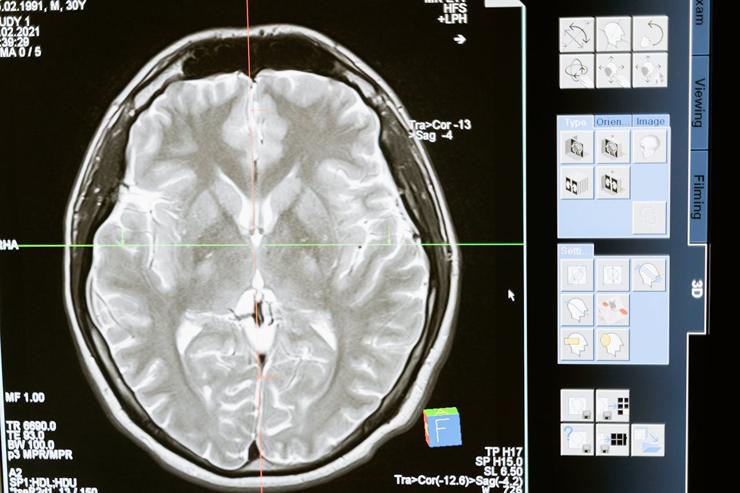

Patiënten met agressieve hersenkanker (graad 3-glioom) krijgen geen protonentherapie meer. De protonenbehandeling voor deze specifieke vorm van hersenkanker is stilgelegd, zo blijkt uit onderzoek van onder meer NRC en Follow The Money. Deze patiënten blijken namelijk een vijf keer hogere kans te hebben op overlijden dan patiënten die dezelfde diagnoses kregen, maar behandeld werden met radiotherapie.

De protonenbestraling blijkt bij agressieve hersentumoren inferieur aan de klassieke radiotherapie. Het risico op vroegtijdig overlijden is vijf keer zo groot als bij patiënten die met conventionele fotonen zijn bestraald, zo blijkt uit data over de periode 2018 en midden 2022. En dat terwijl patiënten juist een veiligere behandeling werd beloofd. De bewijsvoering was echter altijd al wankel en daar is door onder meer ambtenaren van VWS ook al voor gewaarschuwd ten tijde van het oprichten van de centra. Dankzij een krachtige campagne van de radiotherapeuten zijn deze bezwaren terzijde geschoven, blijkt uit onderzoek van Follow the Money.

Protonentherapie is een veelbelovende, maar nauwelijks bewezen bestralingsvorm. Ook FMT Magazine besteedde al eens aandacht aan deze technologie. “Protonentherapie past naadloos in dat streven om nauwkeuriger de tumor te raken en het omliggende weefsel zo veel mogelijk te vrijwaren van straling”, vertelde Sophie Bosma, radiotherapeut in het Holland PTC, bij die gelegenheid. “Als een tumor heel dicht bij kwetsbare organen ligt kan protonentherapie meerwaarde hebben. De dosis op gezond weefsel en daarmee de kans op bijwerkingen verkleint, terwijl de dosis in de tumor gelijk is.” Er is vanaf 2009 veel reclame gemaakt voor protonentherapie en ingezet op meerdere dure protonencentra die veel patiënten zouden gaan behandelen. Al enkele jaren geleden werd duidelijk dat de patiëntenaantallen achterbleven en dat de modellen op basis waarvan patiënten met verschillende vormen van kanker naar deze behandelcentra gestuurd werden, regelmatig wankel waren.